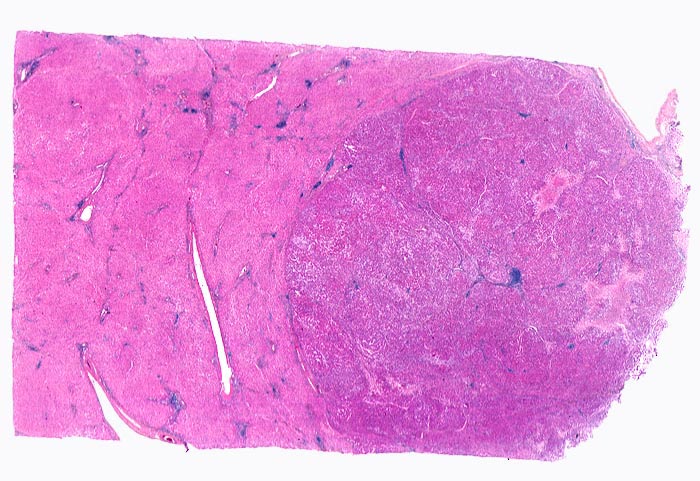

Beschreibung

Das Leberparenchym links im Bild zeigt entzündlich infiltrierte und fibrosierte Portalfelder als Folge der chronischen Hepatitis C. Der scharf begrenzte Tumor rechts im Bild ist aufgrund der höheren Kern-Zytoplasmarelation dunkler gefärbt. Im Tumor finden sich lediglich Arterien, aber keine Portalfelder. Fokale Tumornekrosen und intratumorale Entzündungsinfiltrate.

Das hepatozelluläre Karzinom kann scharf oder unscharf begrenzt sein. Scharf begrenzte Tumoren können bekapselt sein. Die Tumorknoten können solitär oder multipel sein und im letzteren Fall wie ein zirrhotischer Umbau imponieren.